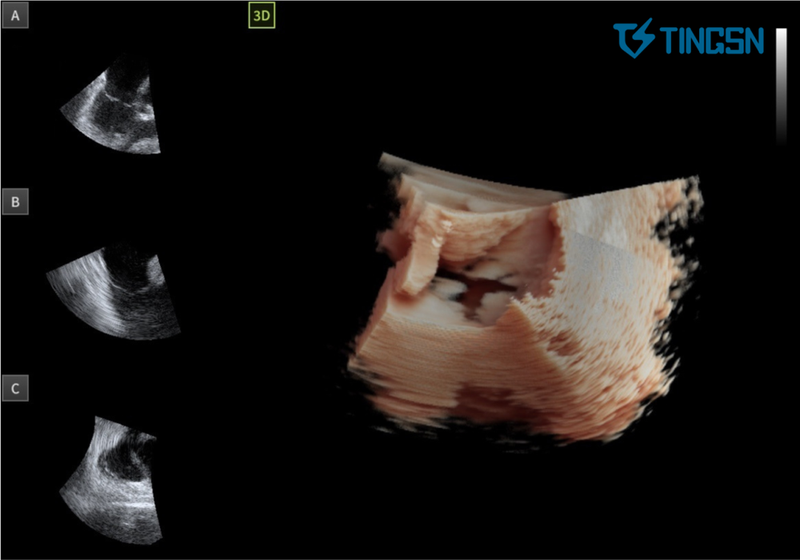

术中穿刺后,术者操作TINGSN 4D ICE导管经股静脉入路,进入右心后观察各腔室结构及瓣膜情况。在4D ICE引导下完成房间隔穿刺,并观察术前心包。建立通路后,首先行肺静脉隔离术,然后在实时动态三维超声影像监测下观察左心耳,引导封堵器械进入并完成封堵。完成干预后,撤出输送系统,并通过二维及三维图像确认心包完整。术后患者体征平稳,转入病房。相较传统X线透视,ICE技术使辐射暴露时间缩短62%,手术总耗时减少约30分钟。

"重构的心腔内立体实时影像与心腔内二维超声影像精度匹配,同步实现360°全景观察。"孔祥清教授特别指出,"这种多维信息整合能力对降低并发症发生率和提高手术消融效率具有重要价值。"临床团队反馈,该设备在瓣膜反流评估、心耳分叶测量等关键环节的成像质量,已达到国际主流产品水平。

01 心室收缩期 三尖瓣瓣叶呈闭合状态

02 心室舒张期 三尖瓣瓣叶呈开放状态

03 左心耳封堵

04 二尖瓣